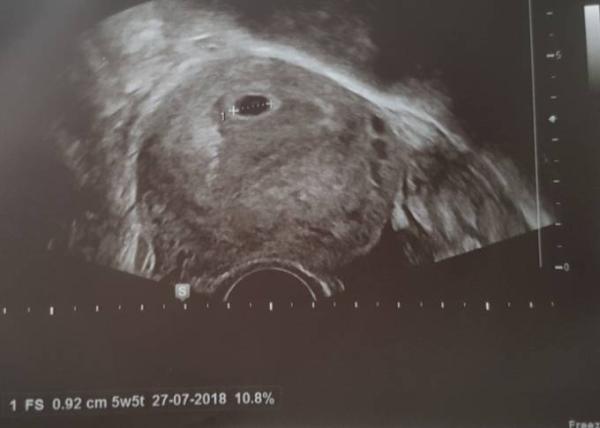

Hatte heute wieder einen FA Termin nach dem ich doch letzte Woche Mittwoch bei ihr war wegen Bauchschmerzen. Da sah die Frucht Höhle gar nicht gut aus. Habt lang wie ein Schlauch. Sie hat mir keine Hoffnung gemacht und ich habe nun 5 Horror Tage hinter mir. Heute wieder Ultraschall und siehe da alles in bester Ordnung. Frucht Höhle ist rund und man konnte schon einen Schatten sehen. Pc rechnet mich auf 5+5 Aber kann eigentlich maximal 5+2 sein. Nächste Woche hab ich nochmal einen Termin dann müsste alles zu sehen sein. Bin so erleichtert. Die letzten Tage waren schlimm